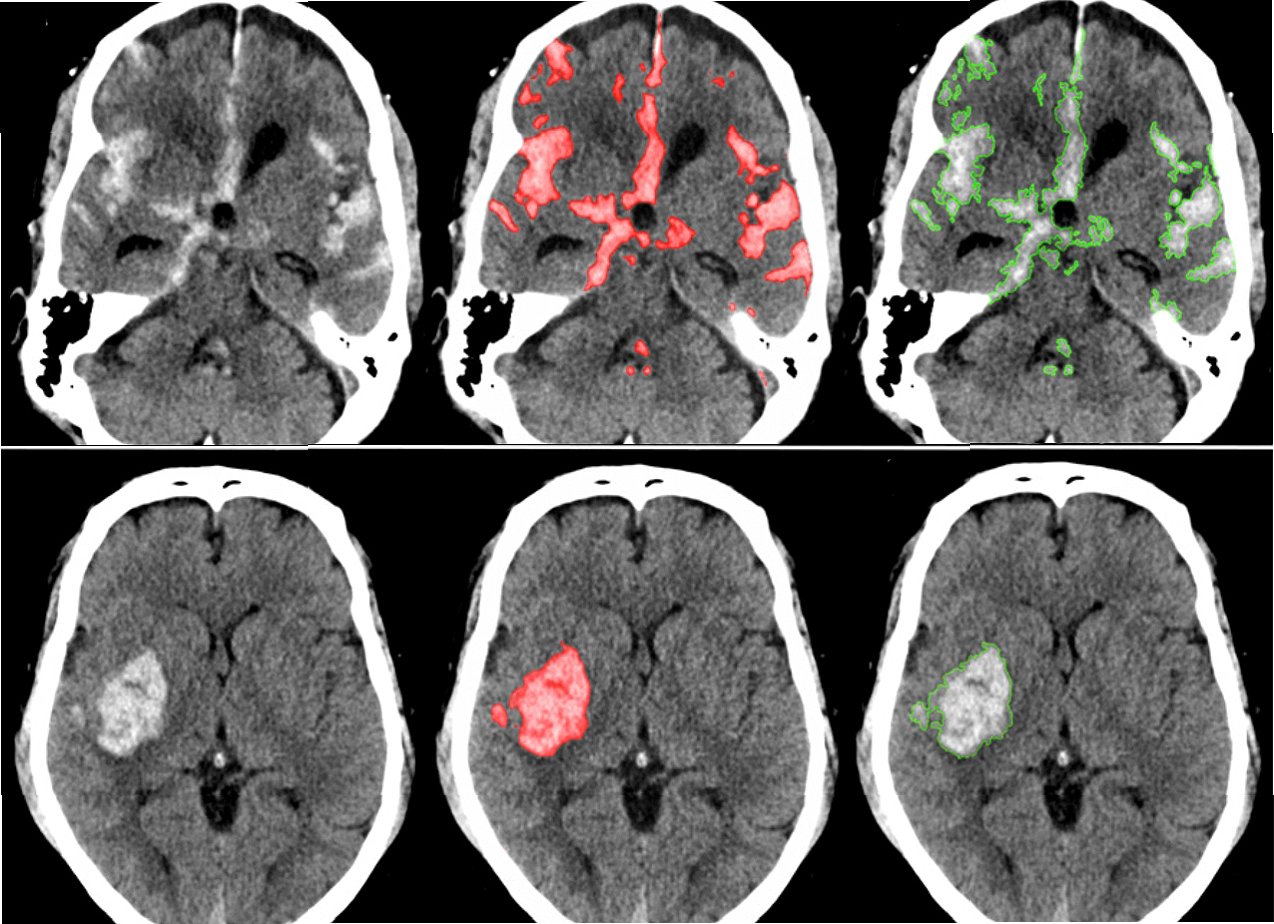

인공지능(AI) 기술은 뇌졸중 진단과 치료 분야에서 괄목할 만한 발전을 이루고 있습니다. AI 기반의 영상 분석 기술은 뇌 CT, MRI 등의 의료 영상에서 미세한 변화를 감지하여 뇌졸중의 조기 진단을 돕습니다. AI는 뇌졸중의 유형, 위치, 심각도를 빠르고 정확하게 파악하여 의료진의 의사 결정을 지원하며, 치료 계획 수립에 기여합니다. AI 알고리즘은 뇌졸중 환자의 예후를 예측하고, 맞춤형 재활 치료 계획을 수립하는 데 활용됩니다. AI 기술은 뇌졸중 환자의 생존율을 높이고, 후유증을 최소화하는 데 기여하며, 의료 서비스의 효율성을 향상시킵니다. AI 솔루션은 뇌졸중 치료의 새로운 지평을 열어가고 있습니다.

1. 조기 진단: AI는 의료 영상을 분석하여 뇌졸중의 징후를 조기에 감지합니다.

2. 정확한 진단: AI는 뇌졸중의 유형과 심각도를 정확하게 파악합니다.

실제 의료 현장에서 AI 기반 뇌졸중 솔루션의 활용 사례가 증가하고 있습니다. AI는 응급실에서 뇌졸중 의심 환자의 CT 영상을 분석하여 뇌출혈 여부를 빠르게 판단하고, 의료진에게 신속한 치료 결정을 돕습니다. AI는 뇌졸중 환자의 재활 치료 과정을 모니터링하고, 환자의 회복 속도에 맞춰 맞춤형 재활 프로그램을 제공합니다. AI 기반의 원격 의료 시스템은 뇌졸중 환자가 거주지에서 전문적인 의료 서비스를 받을 수 있도록 지원합니다. AI 기술은 의료진의 업무 부담을 줄이고, 환자 중심의 의료 서비스를 제공하는 데 기여합니다. AI 솔루션은 의료 자원이 부족한 지역에서도 뇌졸중 환자에게 효과적인 치료를 제공할 수 있도록 돕습니다.